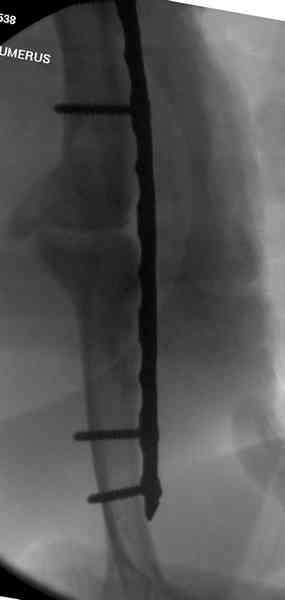

Первичную пластину убрали недели 6 назад из переднего оригинального доступа, и из-за подозрительности тканей вокруг пластины, решили провести реконструкцию поэтапно.

После промывки и дебридмента для уверенности уложили антибиотический цемент. Культура из раны в последующем была отрицательная.

Хотя сам не стороннник применения более массивных

имплантов для плеча, но для этого случая сделали

исключение. На снимке 4А диаметр мягких ткани около 20 см, при весе больной более 135 кг, и также выступление Андрея Волны подстегнуло к применению более массивной 4.5 мм локинг пластины.